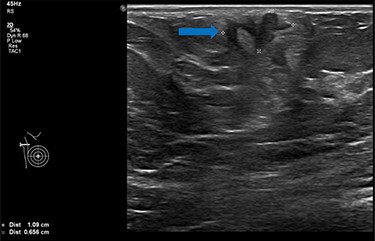

She underwent triple assessment. Bilateral mammogram showed no abnormality in either breast. However, right axillary accessory breast tissue had notably increased in size since her previous mammogram (7 months earlier) and displayed slight distortion (R3) (Fig. 1). Ultrasound scan of the right axilla showed accessory breast tissue measuring 56 × 50 mm in its maximum dimension without any abnormal axillary lymph nodes. Furthermore, the palpable lump showed indeterminate characteristics (U3) measuring 10.9 × 8.3 mm (Fig. 2). Ultrasound-guided core biopsy of the abnormality showed Grade 1 mucinous adenocarcinoma (Fig. 3) which was oestrogen and progesterone receptor positive (Quick score of 8) and Her-2 negative. There was no evidence of lymphoid tissue in the core biopsy.

Bilateral mammogram shows mixed density glandular breast tissue with no focal abnormality within the breast. The right accessory breast tissue had increased in size and density (red arrow) from her previous mammogram with distortion and indeterminate imaging appearance, M3 (Royal College of Radiologist, Breast Group Classification).